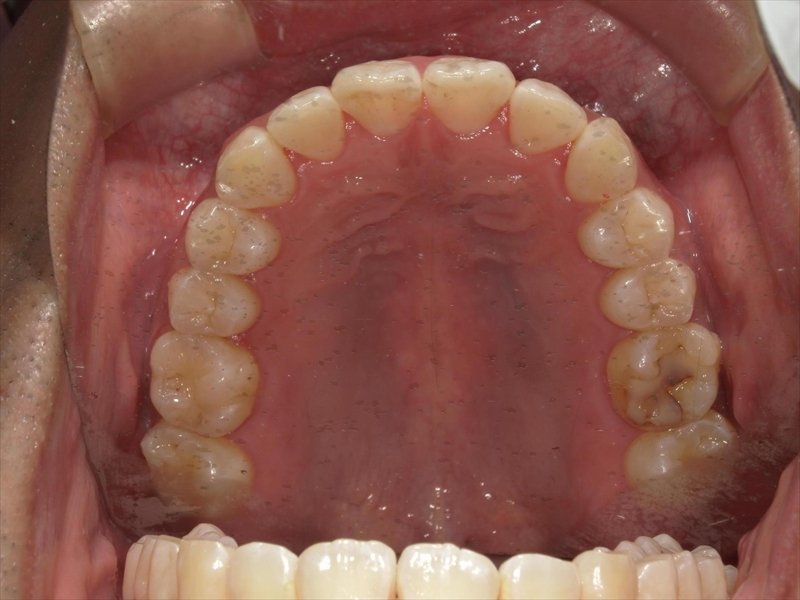

上顎について

前歯のねじれ(V字)と出っ歯を下げるスペースを確保のため、両側1~5番目を0.2~0.5ミリ(計4ミリ)削ることと、奥歯から順に奥へ下げながら外側へ広げる計画を立案しました。

治療前後 写真